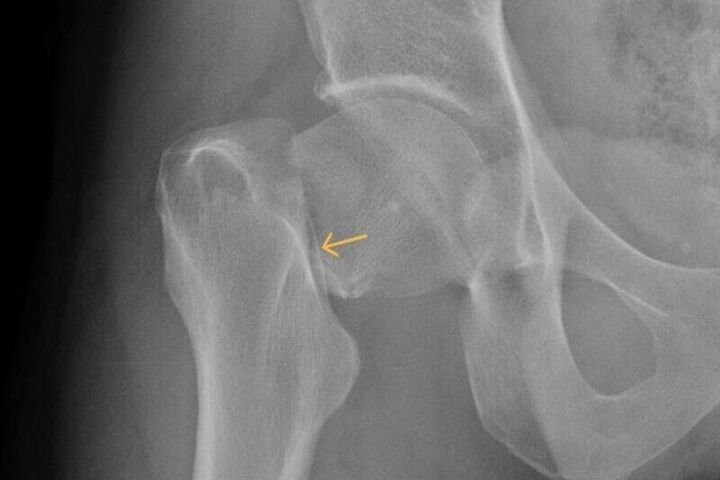

В Новокузнецке врачи городской больницы имени Г.П. Курбатова допустили грубую ошибку — не распознали у пациента перелом шейки бедра. После обращения мужчины, получившего травму при падении на улице, медики ограничились поверхностным осмотром и поставили неверный диагноз — «растяжение связок».

Несмотря на сильную боль, мужчине назначили амбулаторное лечение, а вскоре и вовсе закрыли больничный лист, направив его обратно на работу. Симптомы тем временем усиливались, и лишь спустя полтора месяца компьютерная томография показала — у пациента тяжёлый перелом.

Эксперты страховой компании «Альфа-Страхование-ОМС» установили: при осмотре врачи нарушили стандарты диагностики. Материалы проверки передали в правоохранительные органы, которые добились проведения судебного разбирательства.

Суд частично удовлетворил иск пострадавшего. Больница обязана выплатить мужчине 150 тысяч рублей компенсации морального вреда.